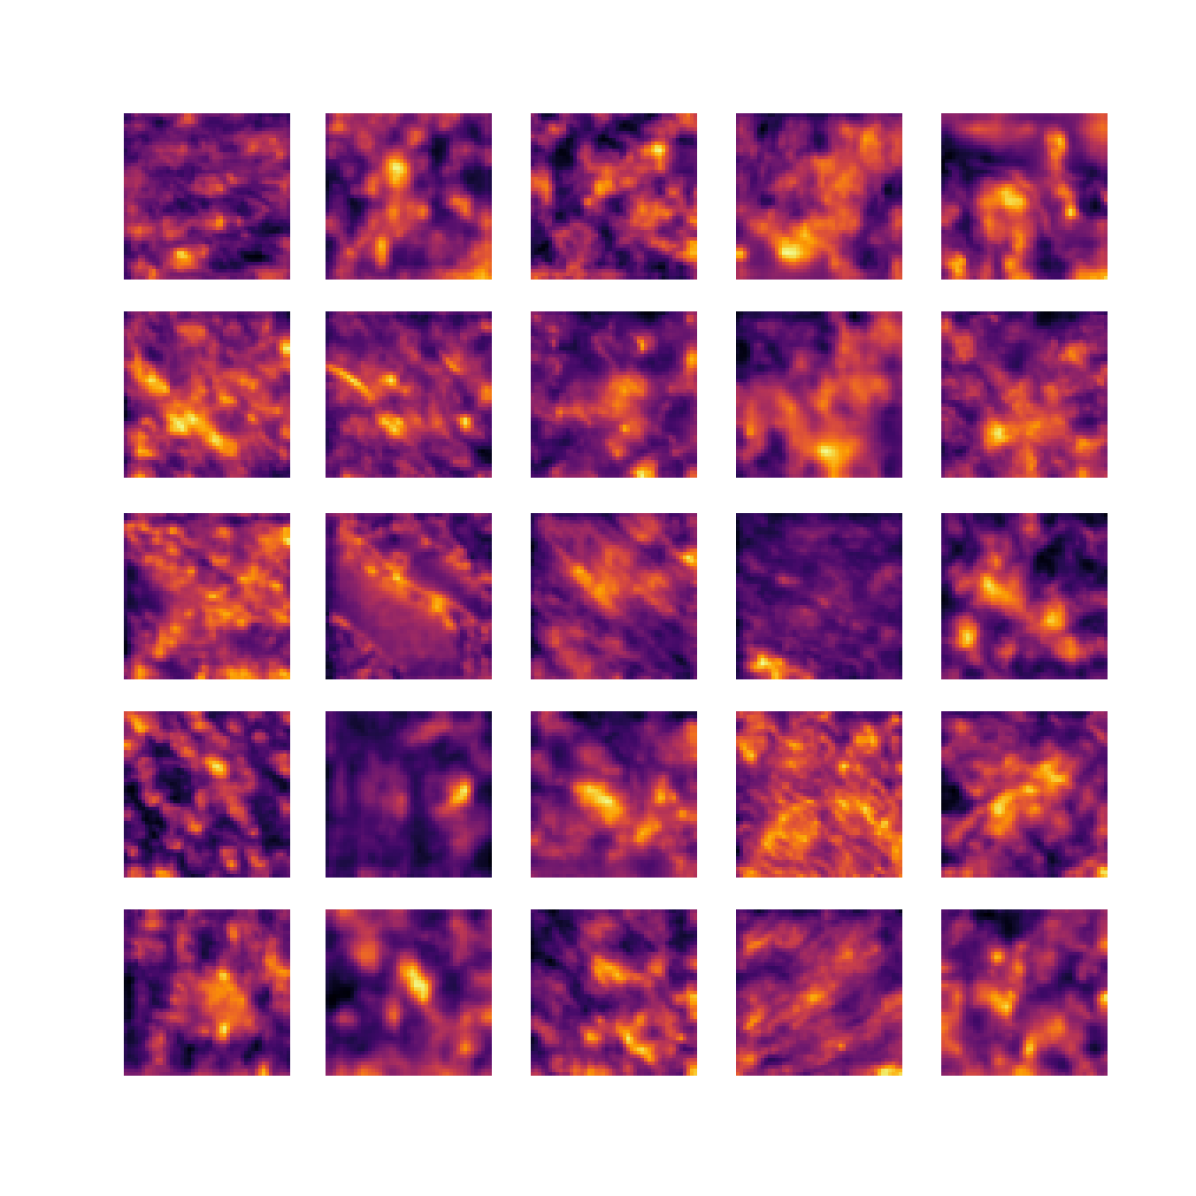

We also analyse the activation maps for each model using GradCAM as described in section S3. This offers more insight into the areas of the image which are contributing most heavily to the models’ representations. In Figure 4(b) we present some representative examples, however, a larger selection which was chosen at random is presented in Figures S10 to S25. The larger selection makes it easier to see the emergent patterns, including that privileged Siamese models tend to mainly identify features which are strongly present in both inputs, while unprivileged Siamese models tend to learn more diffuse features that are not specific to one cell phenotype or image region. TriDeNT ♆ incorporates both sets of features, learning both features specific to the privileged data and more the general features associated with unprivileged Siamese networks.

We can see in Figure 4(b) panel A that for ERG, the privileged Siamese model focuses almost exclusively on any nuclei which could be endothelial cells. As there are very few endothelial cells in the dataset, it could be an effective strategy to identify anything that could potentially be an endothelial cell to minimise the difference between the representations of the H&E model and the IF mask model. In the corresponding unprivileged Siamese image, we see that the model identifies some of these nuclei, albeit less strongly, but also focuses heavily on the other tissue and even the background, while strongly fixating on two spots of debris in the center of the image. This model has less ‘incentive’ to learn the weak features related to endothelial cells as these occur rarely and are not easy to detect, while more generic strong features such as the presence of connective tissue and the prevalence of background are more common and predictable from augmented images. We see that TriDeNT ♆ combines these two feature sets, strongly identifying nuclei while also identifying the connective tissue.

In panel C we see a similar pattern, with the privileged Siamese model fixating solely on the nuclei, while the TriDeNT ♆ model takes a more balanced approach. The unprivileged Siamese model appears to focus on a single cluster of nuclei while neglecting others, and similarly identifies an area of fibroblasts with its distinctive pattern but does not others.

In contrast to panels A and C which represent models with poor privileged Siamese results, panels B and D represent models whose privileged Siamese results were comparable to both TriDeNT ♆ and even the supervised baseline. It is therefore interesting to note that there are far more similarities between the privileged Siamese and TriDeNT ♆ models in both cases. Particularly in panel B, TriDeNT ♆ and the privileged Siamese model return virtually identical heatmaps, with both strongly identifying epithelial nuclei and neglecting the same areas of connective tissue. The unprivileged model in this case appears to focus solely on the centre of the image, giving a significantly different heatmap to the other panels.

Panel D again shows the previous pattern, with the privileged Siamese model identifying the features strongly present in the privileged data – fibroblasts – while neglecting the nuclei present. TriDeNT ♆ also strongly identifies the connective tissue, but, unlike the privileged Siamese model, does not completely neglect the nuclei. The unprivileged Siamese model primarily identifies background, and does not appear to identify the nuclei in this example.